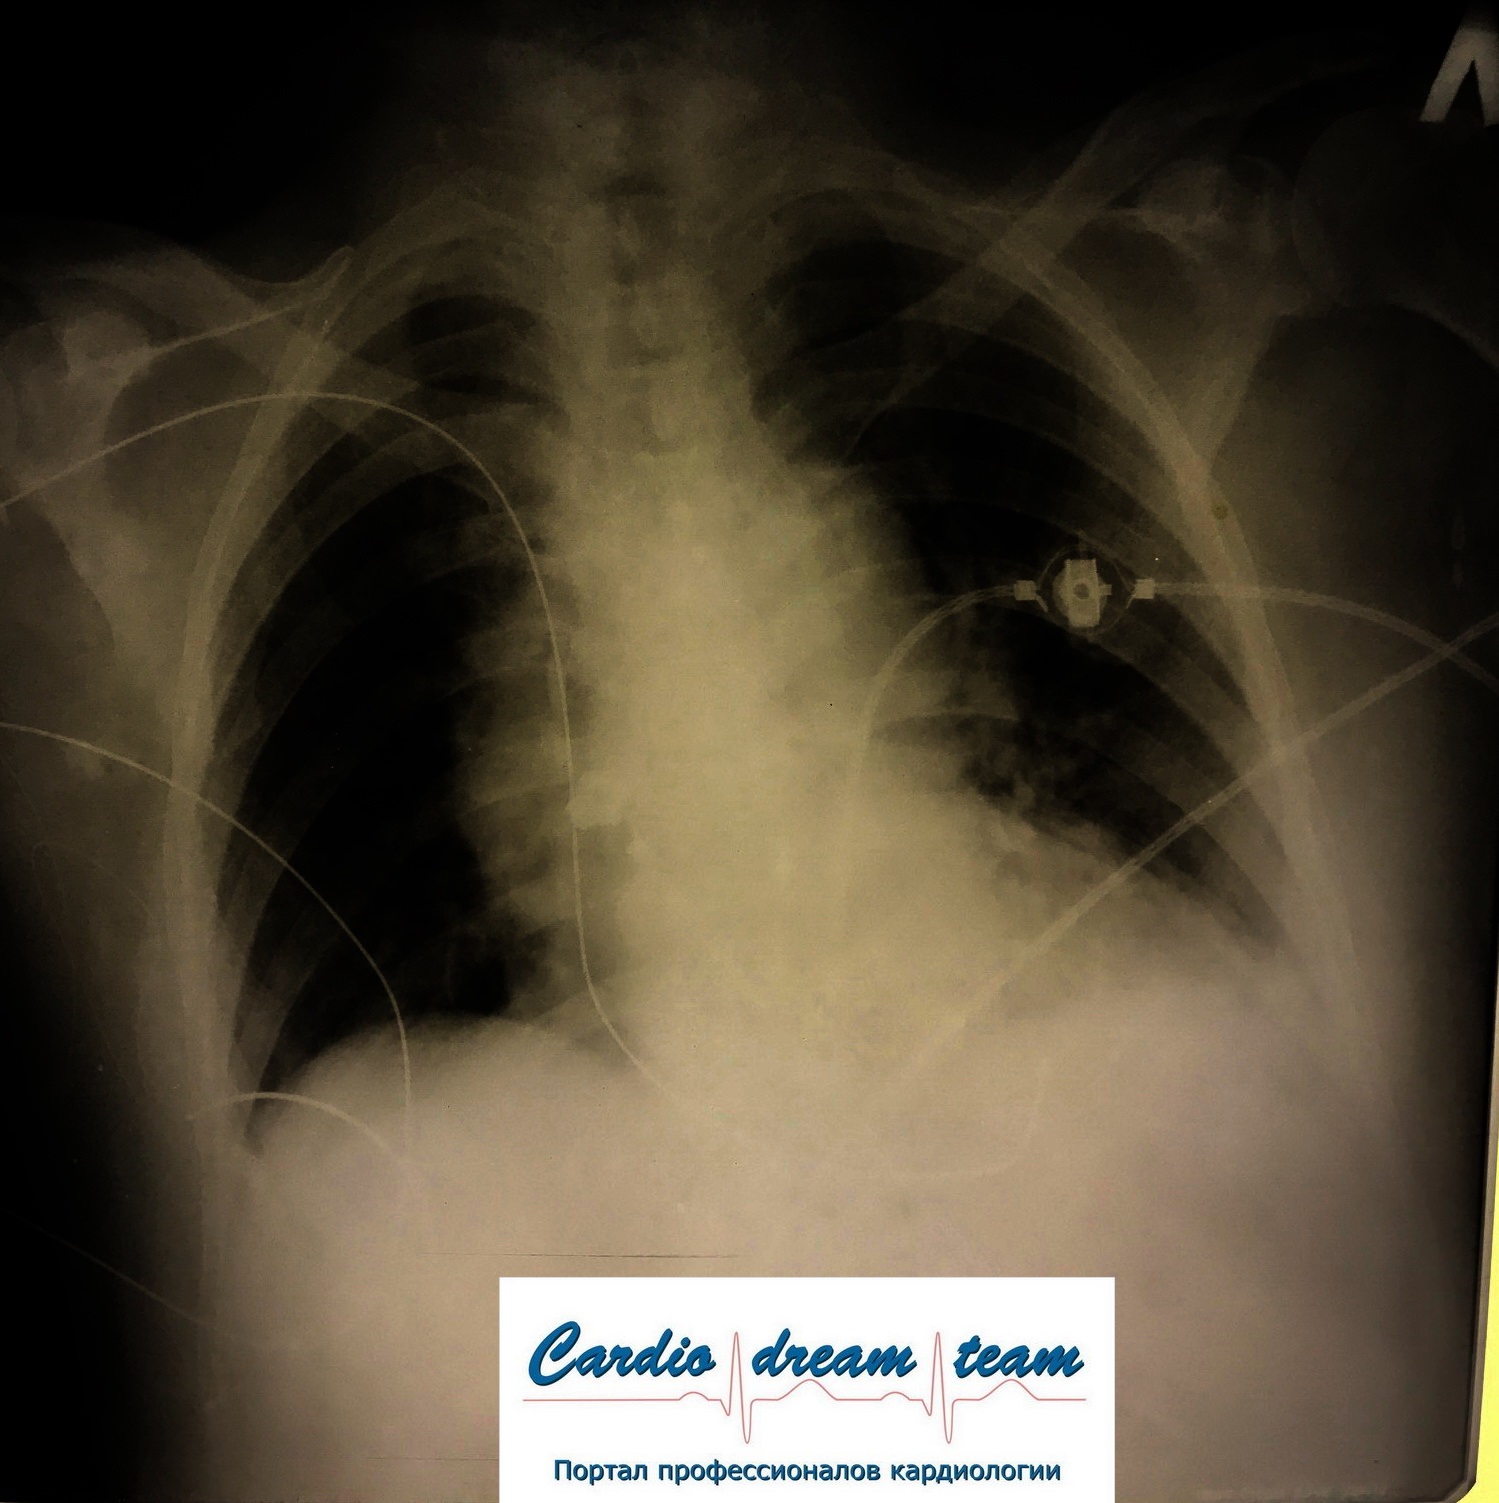

ИКД и оптимизатор у одного пациента

Обсуждалось в Госпитале Ослабленных Сердец